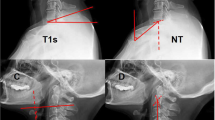

a Normal craniocervical junction in the neutral position. The CXA varies from 150° to 165°. There is minimal or zero deformative strain in the neutral state. b Normal craniocervical junction in flexion. The neuraxis stretches by approximately 10% of its total length with flexion of the craniocervical junction creating a strain ε = 0.1. c Pathological craniocervical junction with an abnormal CXA in flexion. Upon full flexion at the craniocervical junction, the increase in the tangent arc creates a deformative strain approaching ε = 0.2 (i.e., 20% stretch). In vivo and in vitro models demonstrate decreased or loss of neurological function with strains of 0.2

Flexion of the craniocervical junction causes brainstem lengthening, normally by 10% (Fig. 1a–c) [18]. Sawin and Menezes described the “fulcrum effect in basilar invagination, by which traction is applied to the caudal brainstem and rostral cervical spinal cord, producing prominent bulbar dysfunction and myelopathy” [137]. They recognized progression of disability in many patients following suboccipital decompression for Chiari I, attributing the observed brainstem findings to this fulcrum effect [108].